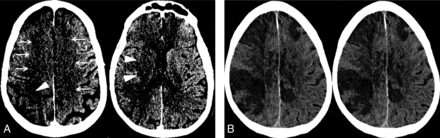

A, Sagittal MIP image from the extracranial CTA performed on the day of admission demonstrates a segmental high-grade stenosis of the proximal right internal carotid artery (arrows). There is normal flow in the right common carotid and external carotid arteries. B, Axial MIP of the intracranial CTA performed on the day of admission demonstrates markedly decreased vascular flow within the branches of the right MCA (arrowheads) and bilateral ACAs (arrows). Conversely, there is normal vascular flow in the left MCA and bilateral posterior cerebral artery territories.

Approximately 5 hours after hospital admission, NCCT revealed large areas of mild hypoattenuation and loss of gray-white differentiation in the territories of the right MCA and bilateral anterior cerebral arteries (ACAs) (Fig 1). Extracranial/intracranial CTA revealed a 20-mm segmental high-grade stenosis of the proximal ICA at the level of the ICA bifurcation (Fig 2). Given that the patient had evidence of mild, diffuse extracranial and intracranial atherosclerotic disease, the high-grade stenosis of the right ICA was favored to represent atherosclerotic disease; however, acute thrombus could have had a similar appearance. The intracranial CTA revealed no large-vessel occlusion, but there was markedly diminished flow in the distal branches of the right MCA and the bilateral ACAs (Fig 2). Approximately 24 hours later, a repeat NCCT revealed worsening cerebral edema and mass effect of the infarcts of the right MCA and bilateral ACA territories, consistent with the expected evolution of acute ischemia (Fig 1).